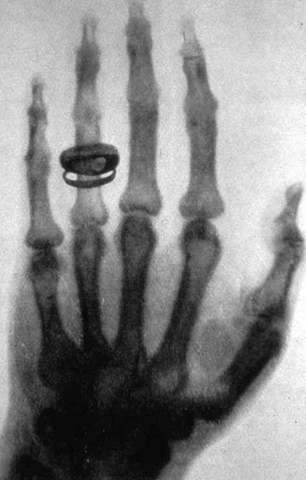

Primera radiografía de la mano de su esposa.